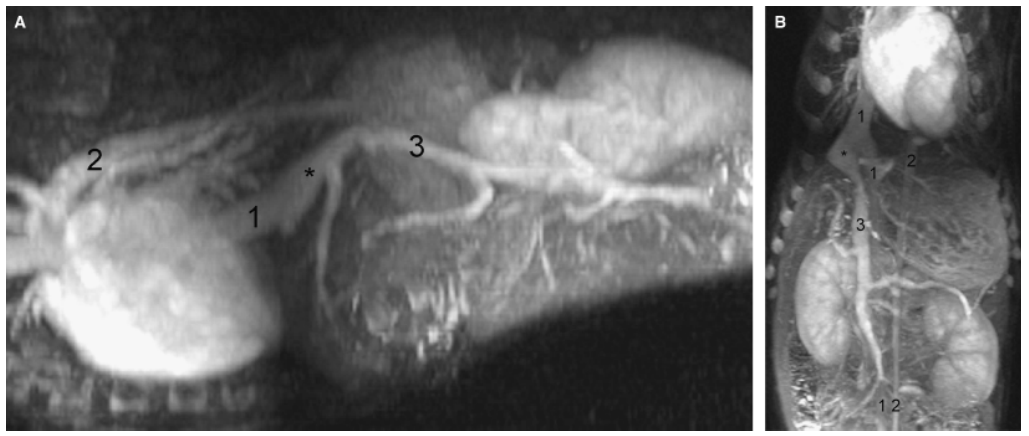

Name the labeled structures and determine the anomaly.

Intrahepatic PSS

Bruehschwein, A., Foltin, I., Flatz, K., et al. (2010) Contrast-enhanced magnetic resonance angiography for diagnosis of portosystemic shunts in 10 dogs. Veterinary Radiology and Ultrasound 51, 116–121